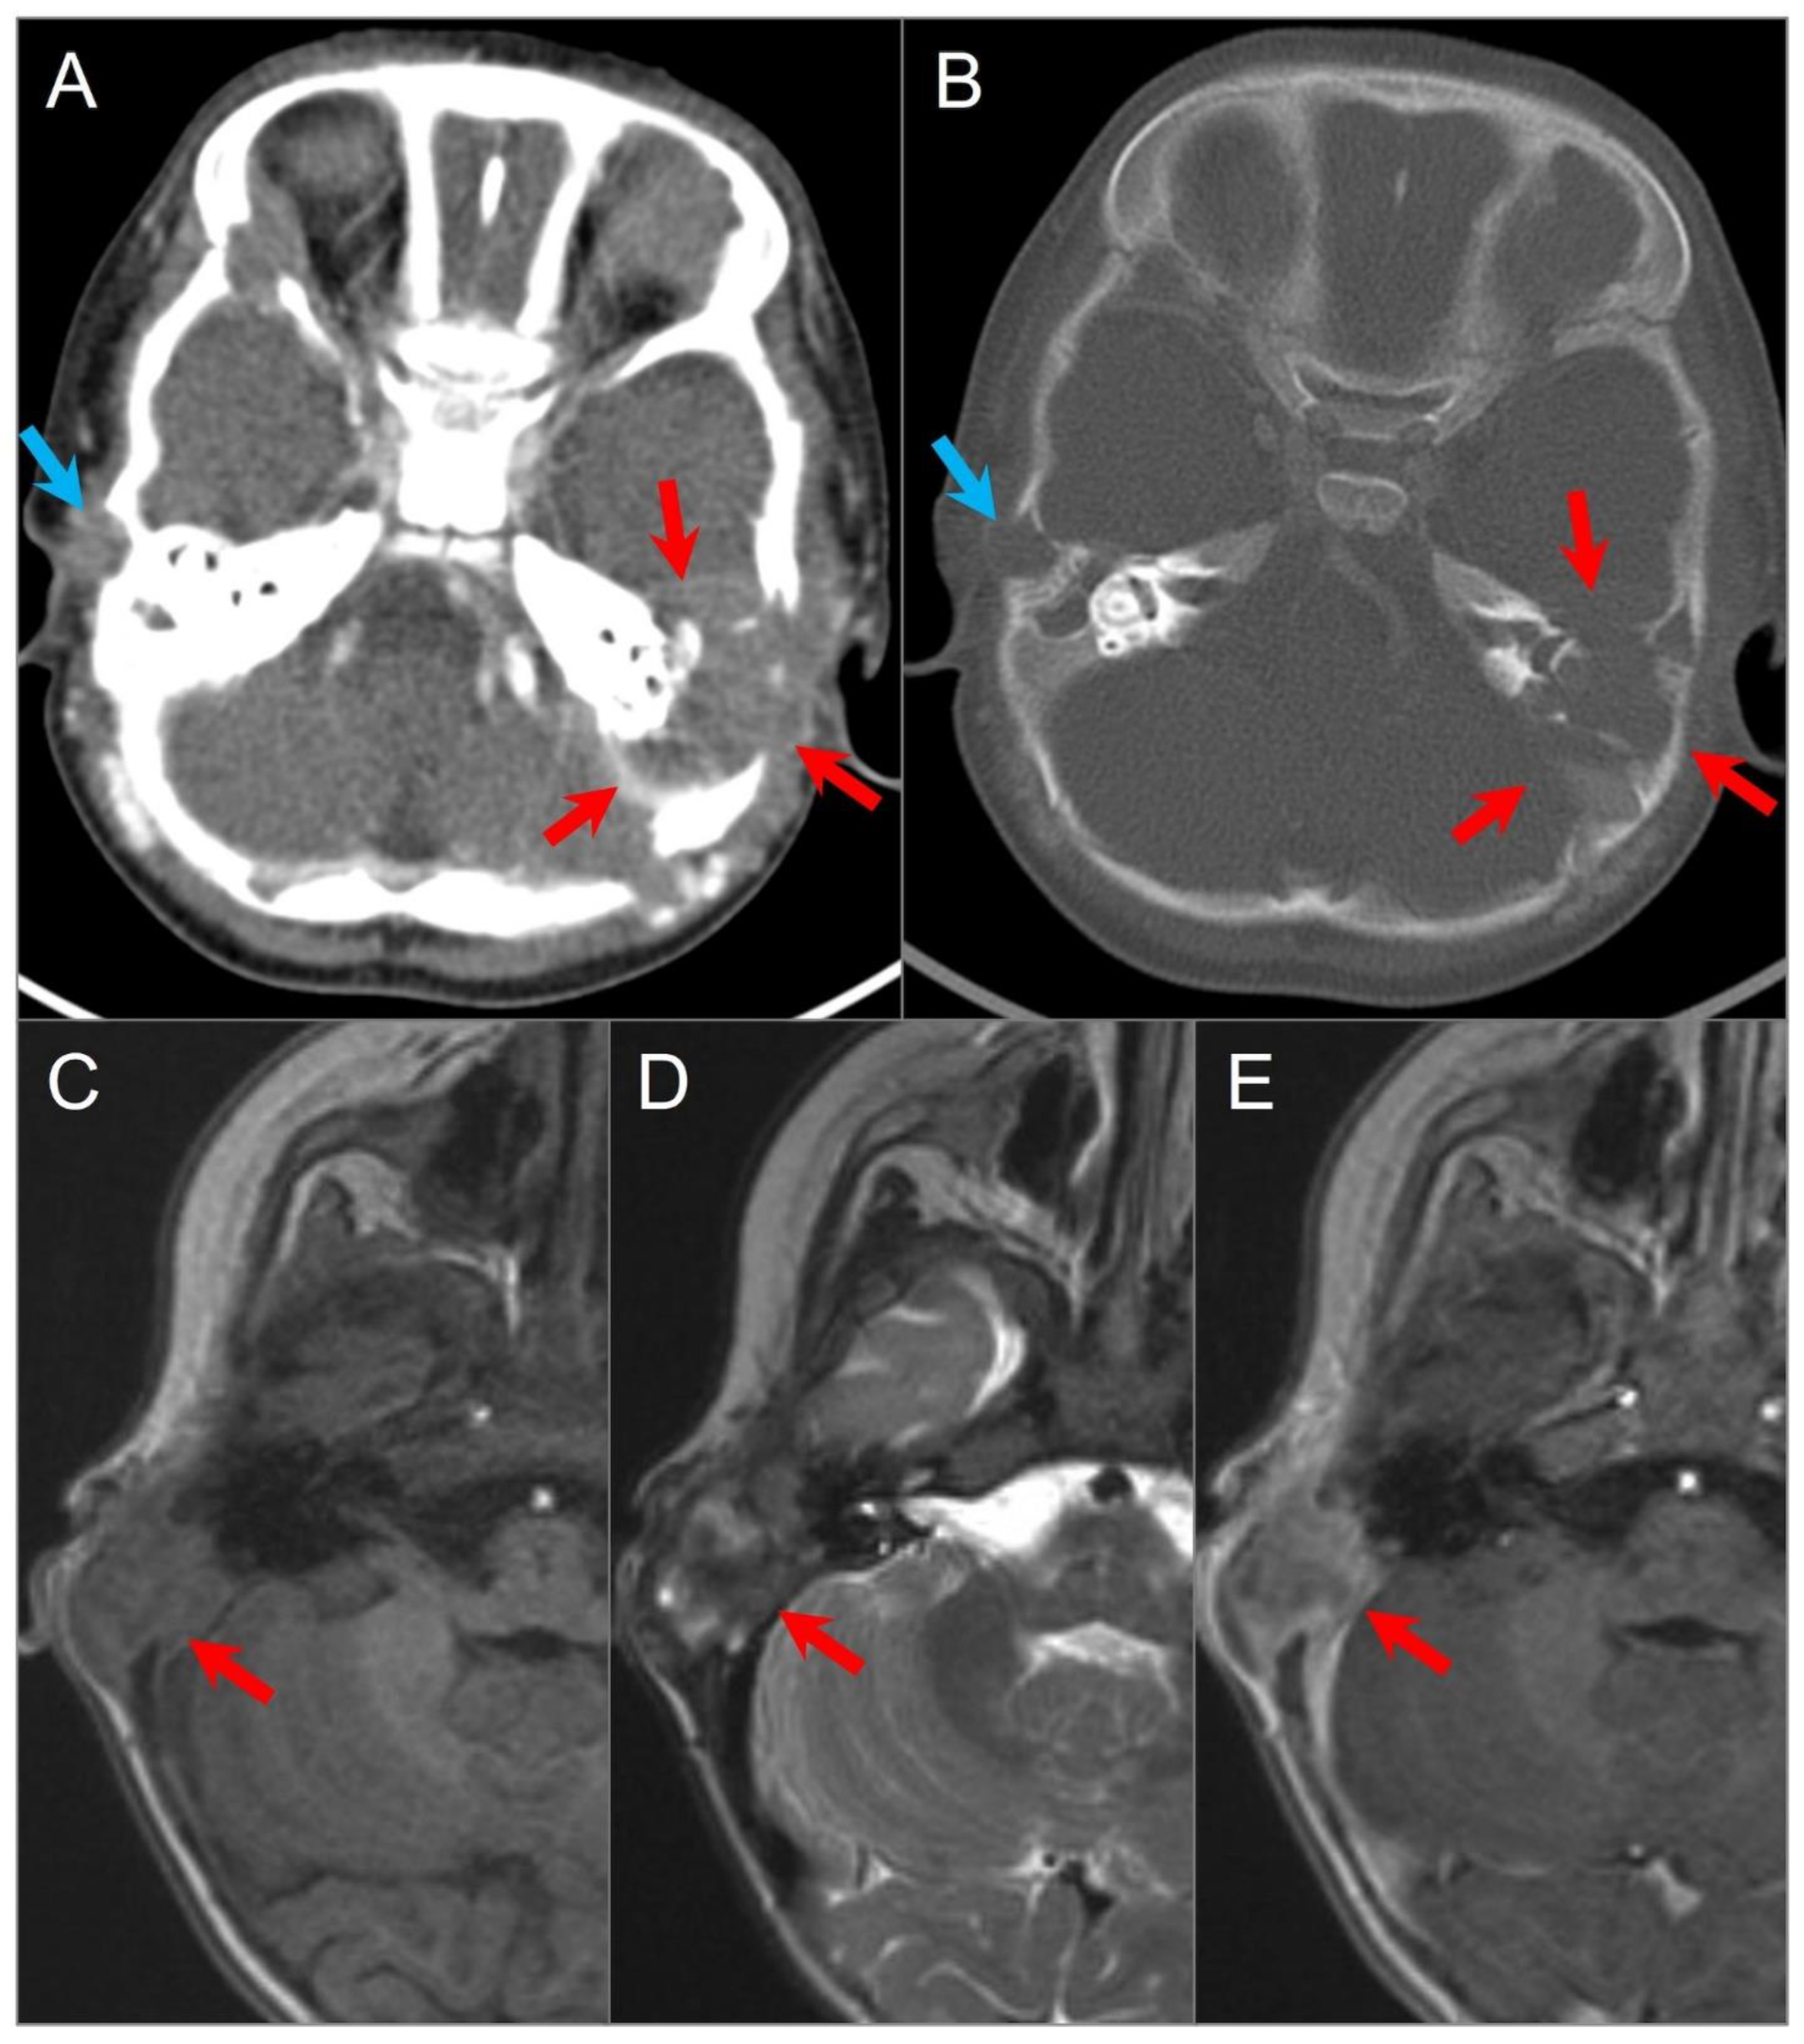

4.1.7. Aneurysmal Bone Cyst